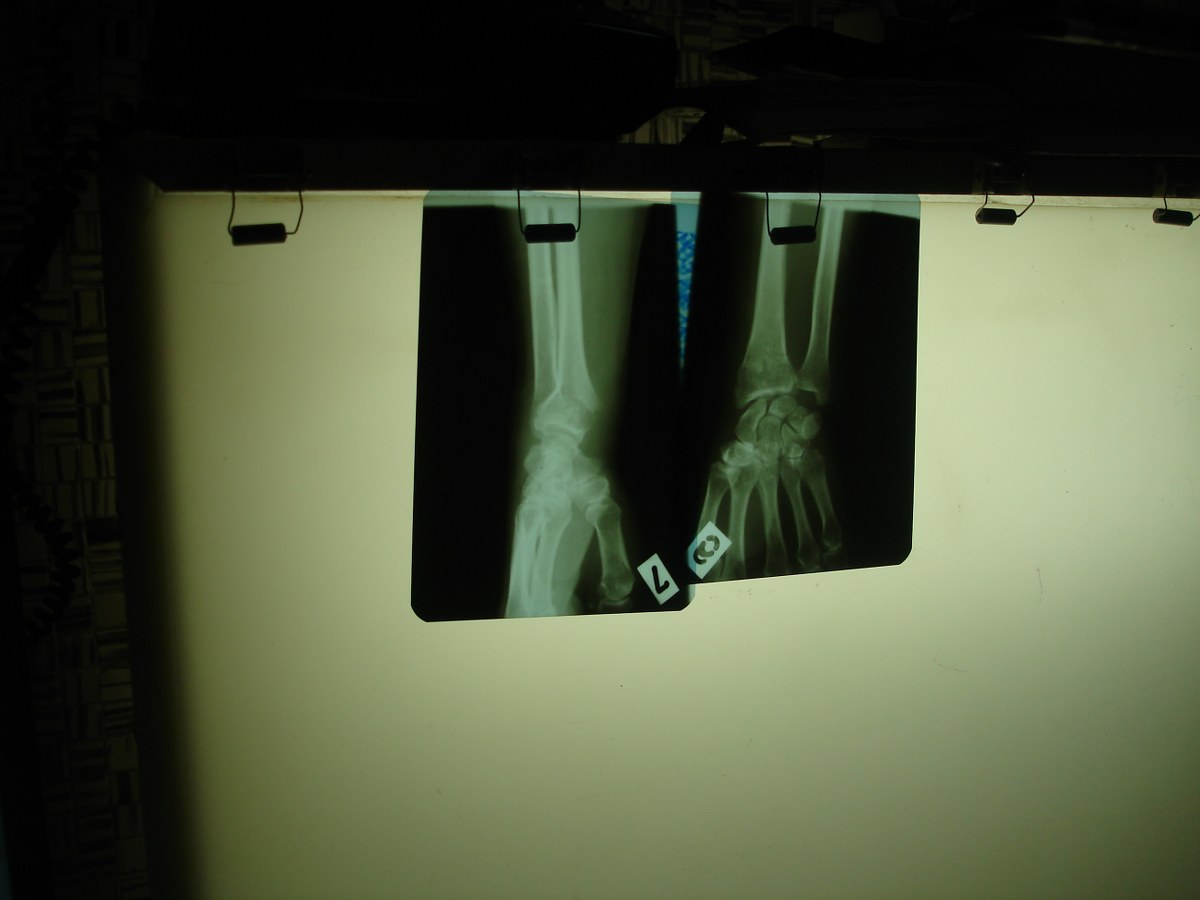

Gheţuşul care a acoperit străzile în ultimele dimineţi a dus la o creştere a numărului de persoane care au ajuns la camera de gardă cu fracturi de mâini, picioare sau şolduri. Bătrânii sunt cei mai afectaţi de această problemă. Astfel, dintre cei peste 160 de pacienţi care ajunseseră până vineri dimineaţă la Spitalul Judeţean, cei mai mulţi erau pensionari. Potrivit doctorului Cătălin Ţâmpău, medic în cadrul Unităţii Primiri Urgenţe, 25 dintre aceşti pacienţi au rămas internaţi, având nevoie de operaţii ortopedice.

Maria Pătraşcu a ieşit vineri dimineaţă la cumpărături cu o pereche de şosete trase peste ghete. Nu i-au fost de prea mare ajutor însă. Două ore mai târziu, zăcea pe o targă în faţa camerei de radiologie. Spune că o doare bazinul şi că ameţeşte atunci când vrea să se ridice. În situaţia ei sunt alţi câţiva pacienţi, care stau la rând pentru consultul medical. Unii însoţiţi de rude, alţii singuri şi dezorientaţi. Cei care au avut totuşi un dram de noroc trec pe la camera de ghipsat şi pleacă apoi spre casă. Ceilalţi rămân internaţi la ortopedie, unde sunt programaţi apoi pentru operaţie.

Şi salvările din Galaţi au transportat în ultimele zile la spital mai multe persoane cu fracturi sau cu răni provocate în urma căzăturilor. "Numărul pacienţilor cu fracturi a crescut cu aproximativ 50 la sută în ultima perioadă. Sunt persoane cu fracturi la membrele inferioare, lovite la cap sau care acuză dureri toracice", a precizat doctorul Mihai Polinschi, directorul Serviciului de Ambulanţă Judeţean Galaţi. Medicii din serviciile de urgenţă spun că acesta este doar începutul sezonului de căzături. "Dacă ninsorile vor continua şi zăpada care se va topi peste zi va îngheţa pe parcursul nopţii, ne aşteptăm ca numărul pacienţilor cu fracturi să fie în continuare mare", este de părere dr. Cătălin Ţâmpău.